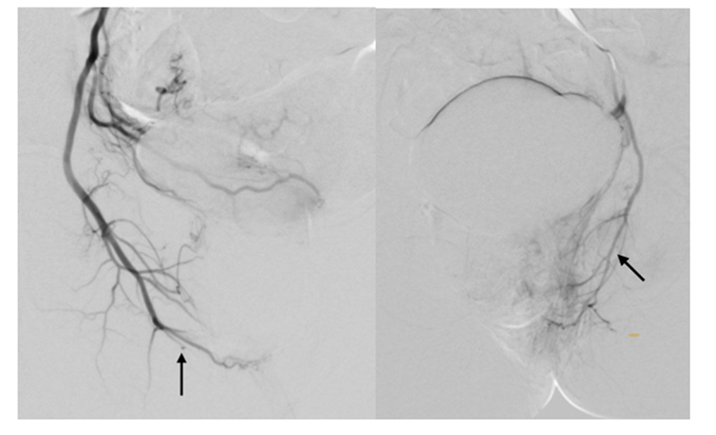

Under infiltration anesthesia with 1 ml of a 2% lidocaine solution, puncture and catheterization of the left radial artery was performed using a 5F introducer. Heparinization – 2500 IU of sodium heparin was administered intra-arterially (through the introducer). Using a hydrophilic 035 4F 150 cm catheter, sequential catheterization and angiography of the right and left uterine arteries (a. uterina), inferior vesical arteries (a. vesicalis inf.), and internal pudendal arteries (a. pudenda int.) were performed (Figs. 3 and 4).

Figure 3: Initial pelvic angiography. The right and left uterine arteries are well contrasted.

Figure 4: Initial pelvic angiography. Right and left internal genital arteries.

Three syringes of EMBOZENE 900 microns embolization microparticles and two syringes of EMBOZENE 1100 microns were used for embolization. A control angiography was then performed. There was prolonged (more than 10 cardiac cycles) stasis of contrasted blood in the branches of the right and left uterine, inferior vesical, and internal genital arteries supplying the pelvic organs (Figs. 5 and 6). At the final stage, a pressure bandage was applied to the puncture site of the radial artery for hemostasis. The total fluoroscopy time was 36 minutes.

Figure 5: Result of embolization of the right and left uterine arteries.

Figure 6: Result of embolization of the right and left internal genital arteries.